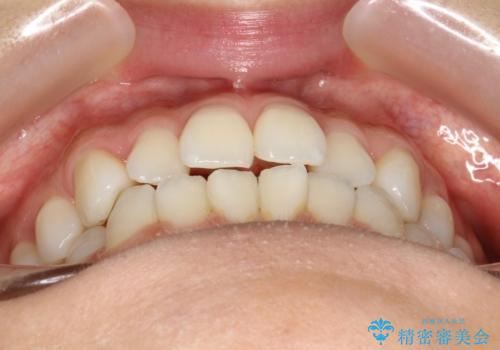

軽度の前歯のガタガタをインビザラインでの目立たない矯正

- 前歯のガタガタを主訴に来院されました。

軽度であったため、枚数制限のあるタイプのインビザラインのプランで治療することとしました。

軽度のガタガタを目立たずに手軽に矯正できるのもマウスピース矯正の魅力といえます。